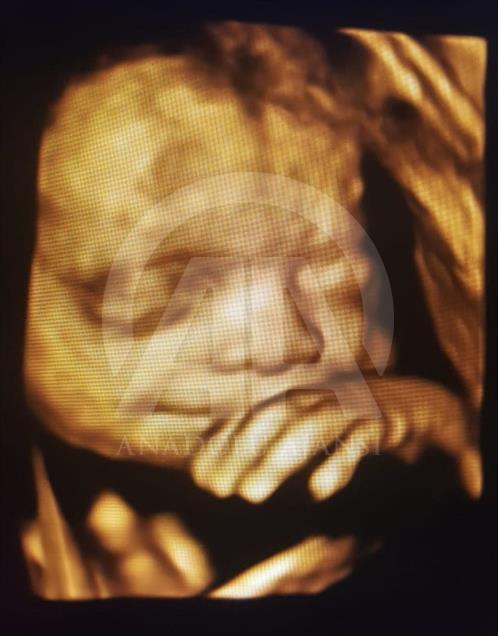

Anne karnındaki bebeklerin ilginç ultrason görüntülerini yakalayan ve bu görüntülerden özel bir köşe oluşturan kadın hastalıkları ve doğum uzmanı Doç. Dr. Gökalp Öner'in, yaklaşık 4 bin fotoğraflık koleksiyonu bulunuyor. Doç. Dr. Öner, AA muhabirine yaptığı açıklamada, sadece bir koleksiyon sahibi olmanın değil, anne ve babalara güzel bir hatıra oluşturmanın mutluluğunu da yaşadığını belirterek, "Doğumdan sonra aileler bizi ziyarete geldiği zaman kendi köşeleri olsun ve orada fotoğraf çektirelim istedik. Böylece, yaklaşık 4 bin ultrason fotoğrafına ulaştık." dedi. ( Müzahim Zahid Tüzün - Anadolu Ajansı )